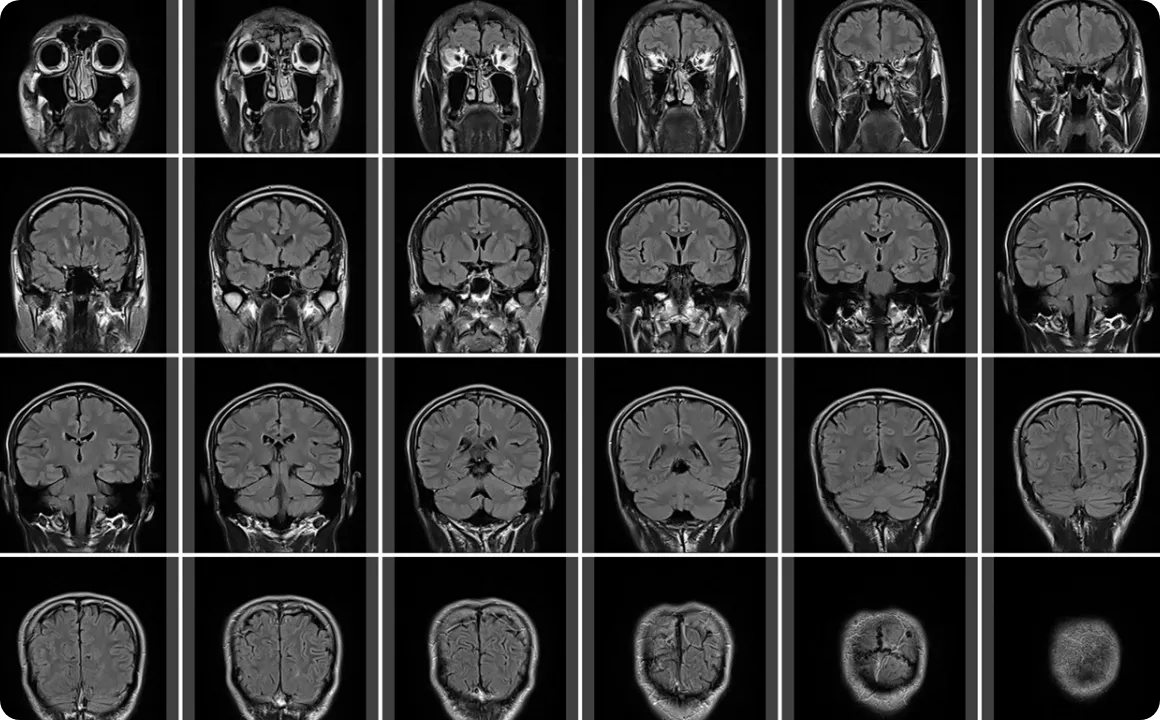

MRI(Magnetic Resonance Imaging)検査とは放射線を使用せず、体内の状態を可視化できる画像診断法です。

磁気と電波によって体のあらゆる部位の情報を画像として映し出します。レントゲンやCTと異なりX線による医療被曝はありません。

従来のレントゲンは2次元の画像で骨や硬い組織の診断に適しているのに対し、MRIでは3次元の画像を生成し軟部組織の異常を詳細に調べることができます。X線やCTスキャンでは見えない軟部組織の細かい構造や状態を詳しく見ることができるため、靭帯損傷などの怪我や関節炎、腱鞘炎など整形外科で多く見られる疾患の有無を確かめる上でとても有効な検査のひとつです。

当院では整形外科領域の診断制度をさらに高めるために、高精度かつ身体への負担も少ない最新の1.5T(テスラ)MRI装置を導入しています。

高感度の専用コイルを使用し関節などの細かい部位までも高精度に撮影。レントゲンやCTでは確認できない微細な損傷も診断可能に。